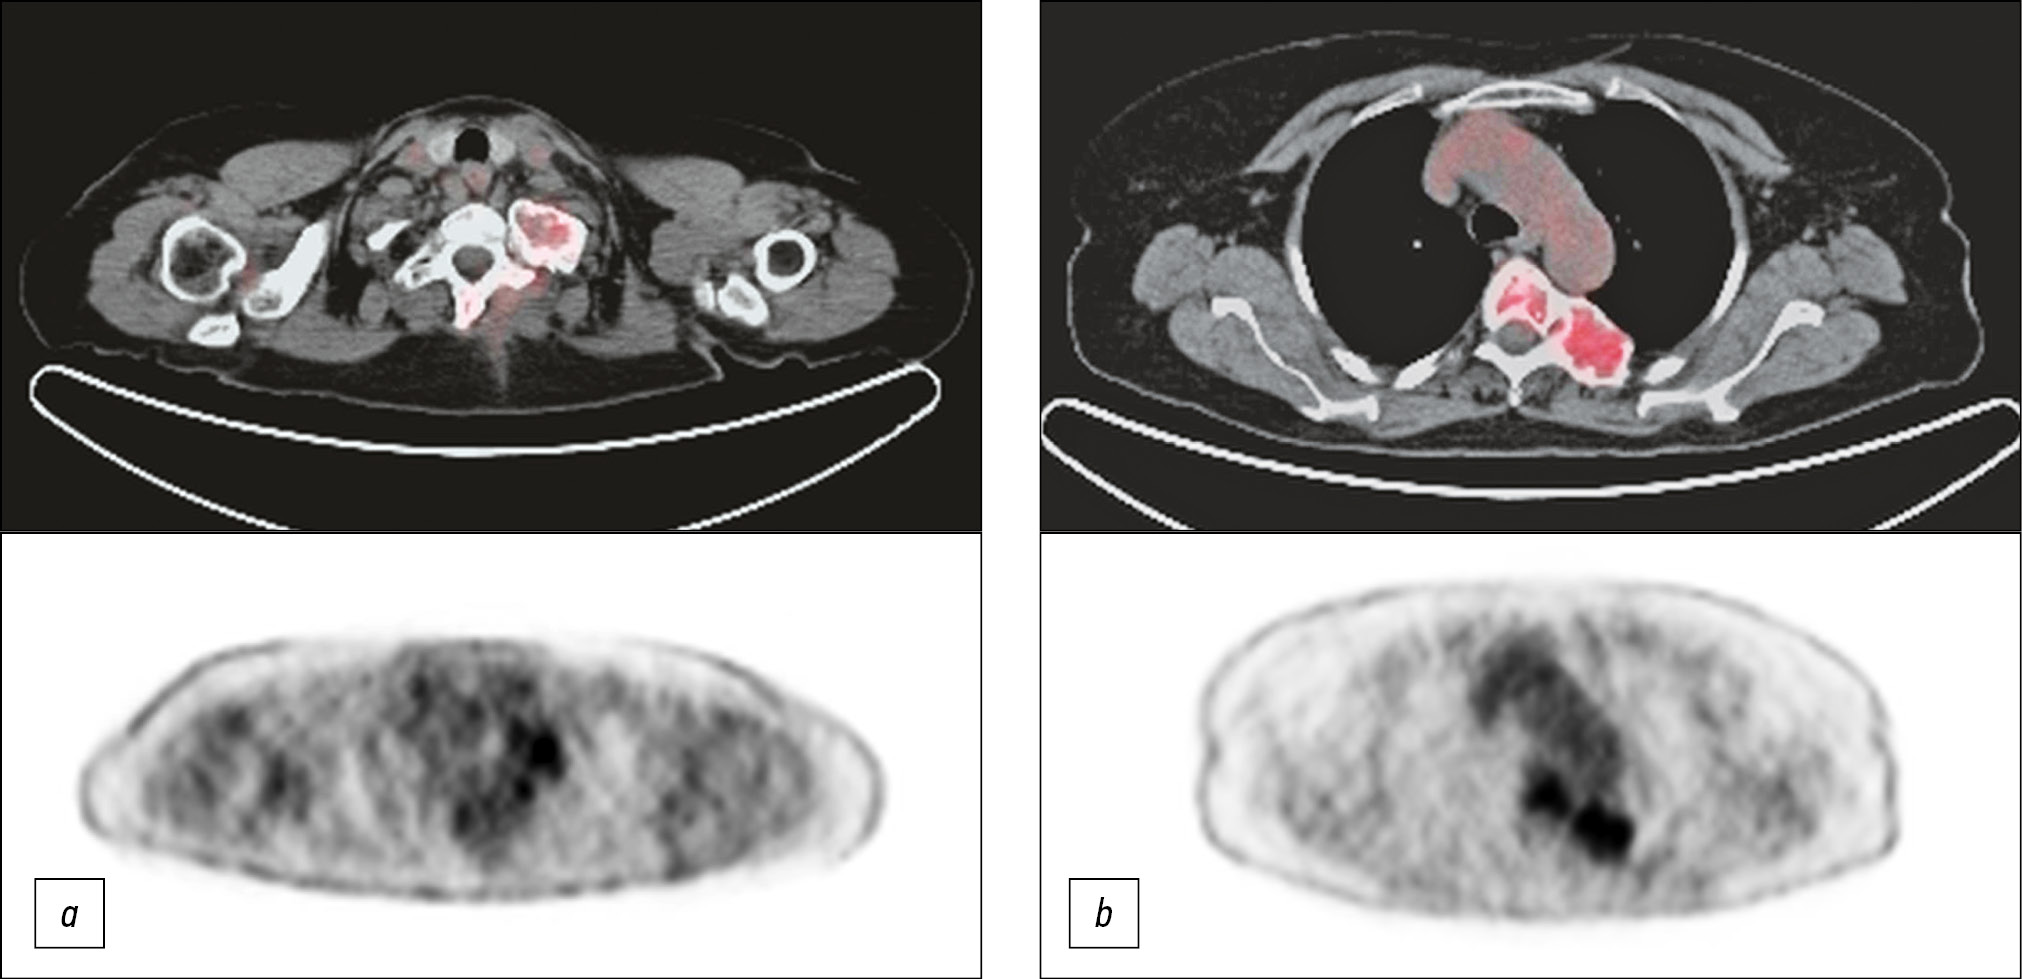

Interdisciplinary databank in oncoendocrinology: radioiodine refractory differentiated thyroid cancer

Abstract

High achievements in personalized evidence-based medicine and oncology, particularly in developed countries, are associated with the successful development of “clinical” carceral registries of patients (SEER, NCDB, etc.), which are multimodal data banks. They are a data matrix for the development of analytical and prognostic tools in the study of diagnostic features, clinical disease course, therapy response, assessment of prognostic factors, etc. From the point of view of medical digital data banks, data redundancy and duplication are not as critical as information incompleteness or inconsistency when making medical decisions.

This study aimed to present a multimodal database of patients with radioiodine refractory differentiated thyroid cancer, which is essentially a modern interdisciplinary digital medical registry.

Along with demographic and nosological data that is typical for epidemiological registers, the multimodal data banks consider key clinical and paraclinical data, such as the results of laboratory, morphological, and instrumental research methods, and various imaging methods, such as ultrasound, computed tomography (CT), magnetic resonance imaging, single-photon emission computed tomography/CT, and positron emission tomography/CT. The multimodal data banks present the molecular genetic profile results of the tumor, of which the clinical usefulness in the choice of treatment tactics is undoubted today. All these data are accumulated in the multimodal data banks, noting the execution time and the revision results (second opinion), considering standardized qualitative and quantitative parameters (factors) that potentially affect the clinical course, treatment response, complication development, and outcomes.

86-93